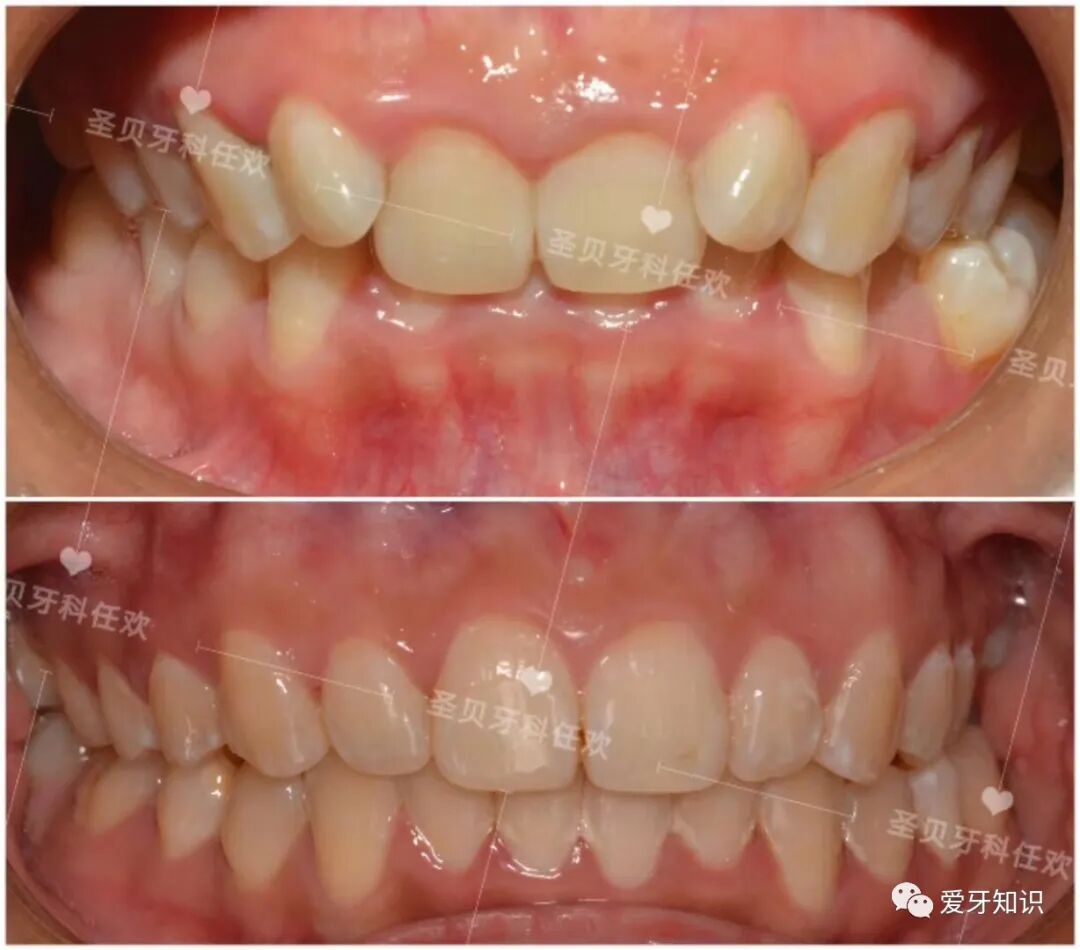

疫情过后,最近有很多小小美女,小帅哥都开始找我摘牙套了!都和牙套说分手了,下面就来给大家看几个摘牙套的小伙伴通过牙齿矫正有多大变化!

先上图给大家看看效果。

关于牙齿矫正每个人的要求都不一样:有的人是改变嘴凸,有的人是改变牙齿拥挤,有的人是改变牙齿咬合,有的人是想对齐中线。等等!

下面再来看看一个小姐姐矫正的变化,矫正改变真的是大,嘴型好看了,皮肤也好看了,你不羡慕吗?

矫正前,

矫正后

矫正前

矫正后!